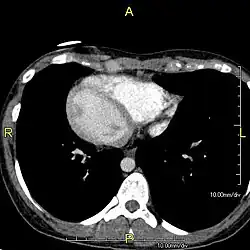

Situs inversus (lat. invertierte Lage) ist der medizinische Ausdruck für das Vollbild einer Heterotaxie, eine seltene, an sich nicht krankhafte Besonderheit der Anatomie, bei der sich die einzelnen Organe spiegelverkehrt jeweils auf der anderen Seite des Körpers befinden. Das Antonym ist der Situs solitus, also die normgerechte Position der Organe im Körper.[1] Synonyme des Situs inversus sind: Inversio viscerum,[2] Situs inversus viscerum, Situs inversus totalis, Situs perversus, Situs transversus, Situs rarior,[3] Situs transversus viscerum,[4] Situs oppositus, Situs inversus completus.

Beim Situs inversus partialis sind nur entweder die Thoraxorgane (also die Herzhälften und die Lungenflügel) oder die Bauchorgane spiegelbildlich quer vertauscht. Beim Situs inversus incompletus besteht keine Dextrokardie. Beim seltenen Situs inversus viscerum specularis ist nur einer von beiden eineiigen Zwillingen betroffen.[5]

Situs inversus bei Menschen

Der Situs inversus (viscerum) tritt bei etwa einem von 8.000 bis 25.000 Menschen und bei der Hälfte der Menschen mit primärer ciliärer Dyskinesie (Kartagener-Syndrom) auf.[6] Bei Menschen mit dieser Heterotaxie befindet sich die Leber beispielsweise auf der linken und im Gegensatz dazu die Milz auf der rechten Seite. Ein auffälliger Anstieg von Fällen wurde einige Monate nach der Aufhebung der Zero-COVID-19-Politik in China beobachtet, was mit einem Anstieg von SARS-CoV-2-Infektionen zusammenfiel. Seltene klinische Hinweise zeigen eine mögliche Folge einer SARS-CoV-2-Infektion bei Schwangeren, speziell in den Schwangerschaftswochen 4–6, dem Entwicklungszeitraum für die Organe des Fötus.[7]

Entsprechend der spiegelverkehrten Lage des Herzens (Dextrokardie, gr. dexios = „rechts“, kardia = „Herz“) müssen die Ableitungen des EKGs angepasst werden; es müssen u. a. in den Brustwandableitungen die Elektroden spiegelbildlich zu Situs-solitus-Patienten am Brustkorb befestigt werden.[8][9][10] Differentialdiagnostisch muss an Verpolungen gedacht werden.[11] Bei einigen Menschen mit Pätau-Syndrom (Trisomie 13) liegt eine Dextrokardie vor, während die übrigen Organe wie üblich angelegt sind. Diese spiegelbildliche Rechtsverlagerung nur des Herzens heißt auch Situs inversus cordis.[12][13] In der Kardiologie unterscheidet man fünf verschiedene Formen einer Malposition des Herzens: Dextrokardie beim Situs solitus, Lävokardie beim Situs inversus, eine Mesokardie mit mittelständigem Herz, eine Dextroposition oder eine Lävoposition bei extrakardialer Ursache und eine Ectopia cordis. Auch ist beim Betrachten eines Röntgen-Thorax-Bildes an eine Dextrokardie oder an eine Rechts-links-Verwechslung zu denken.